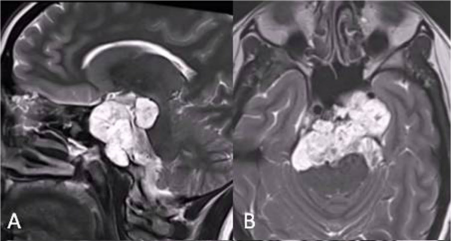

26岁女性,阵发性复视,进行性左外展神经麻痹,MRI显示斜坡较大脊索瘤,病变浸润性生长,肿瘤延伸浸润至乙状窦(SS)、左侧海绵窦(CS)、下斜坡到脑干脚间池硬膜部分(图A、B)。